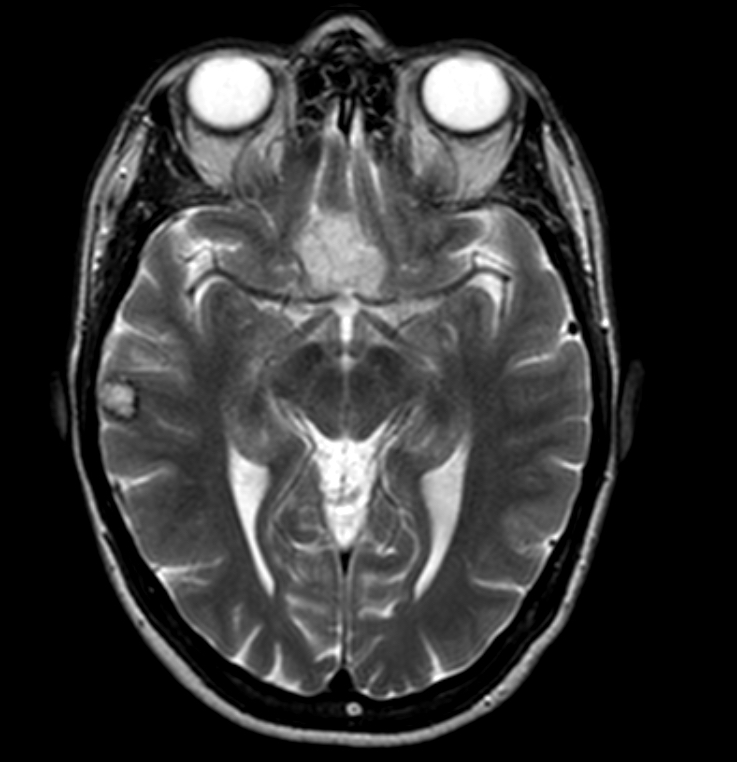

- At MRI, chordoid meningioma is hypoisointense on T1 weighted images and hyperintense on T2 and FLAIR, with contrast enhancement varying from homogeneous to heterogeneous (J Neurooncol 2018;137:575, Neuroradiology 2022;64:253)

- Contrast enhancement is more intense than in meningothelial, transitional or fibrous meningiomas (Neuroradiology 2022;64:253)

- Multicystic appearance is seen in some cases (Neuroradiology 2022;64:253)